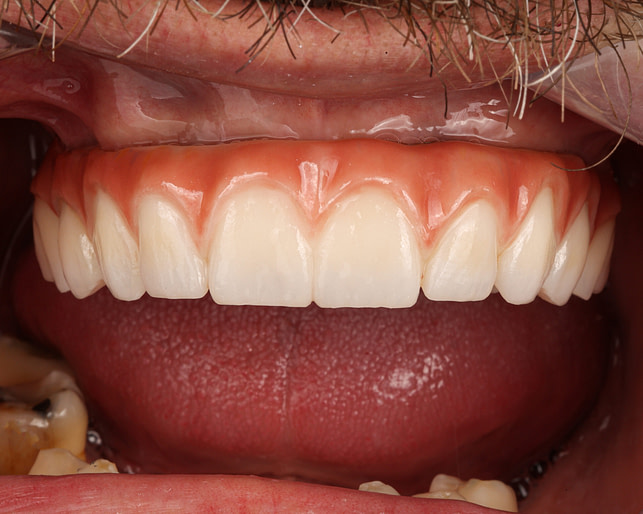

Before

After